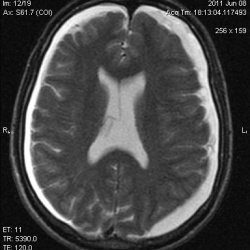

Мужчина.Жалобы на шаткость походки , головокружение.Заболел около 10 дней назад, когда появились вышеуказанные симптомы..А анамнезе около 2-х лет назад-подобное состояние, которое было...

06.06.2011 - 12:42